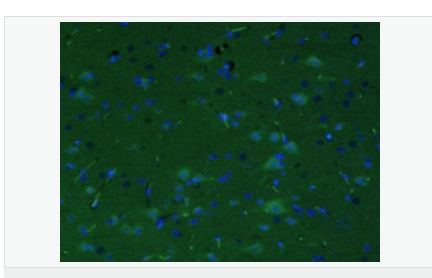

| 產(chǎn)品應(yīng)用 | ELISA=1:5000-10000 IHC-P=1:100-500 IHC-F=1:100-500 IF=1:200-800 (石蠟切片需做抗原修復) not yet tested in other applications. optimal dilutions/concentrations should be determined by the end user. |

| 產(chǎn)品介紹 | This gene encodes a member of the corticotropin-releasing factor family. The encoded preproprotein is proteolytically processed to generate the mature neuropeptide hormone. In response to stress, this hormone is secreted by the paraventricular nucleus (PVN) of the hypothalamus, binds to corticotropin releasing hormone receptors and stimulates the release of adrenocorticotropic hormone from the pituitary gland. Marked reduction in this protein has been observed in association with Alzheimer's disease. Autosomal recessive hypothalamic corticotropin deficiency has multiple and potentially fatal metabolic consequences including hypoglycemia and hepatitis. In addition to production in the hypothalamus, this protein is also synthesized in peripheral tissues, such as T lymphocytes, and is highly expressed in the placenta. In the placenta it is a marker that determines the length of gestation and the timing of parturition and delivery. A rapid increase in circulating levels of the hormone occurs at the onset of parturition, suggesting that, in addition to its metabolic functions, this protein may act as a trigger for parturition. [provided by RefSeq, Nov 2015] Function: This hormone from hypothalamus regulates the release of corticotropin from pituitary gland. Subunit: Interacts (via C-terminus) with CRFR1 (via N-terminal extracellular domain). Subcellular Location: Secreted. Similarity: Belongs to the sauvagine/corticotropin-releasing factor/urotensin I family. SWISS: P06850 Gene ID: 1392 Database links: Entrez Gene: 1392 Human Entrez Gene: 12918 Mouse Omim: 122560 Human SwissProt: P06850 Human SwissProt: Q8CIT0 Mouse Unigene: 75294 Human Unigene: 290689 Mouse Unigene: 10349 Rat Important Note: This product as supplied is intended for research use only, not for use in human, therapeutic or diagnostic applications. CRF陽性神經(jīng)元的胞體廣泛分布于下丘腦的室旁核、背縫核和藍斑核,這些區(qū)域也是去甲腎上腺素(NE)神經(jīng)元與5-羥色胺(5-HT)神經(jīng)元密集的區(qū)域。 CRF既具有神經(jīng)遞質(zhì)的性質(zhì)又具有神經(jīng)激素的性質(zhì)。CRF是聯(lián)系神經(jīng)系統(tǒng)與內(nèi)分泌系統(tǒng)的橋梁,在情感障礙疾患如焦慮和抑郁的發(fā)病中發(fā)揮重要作用. |